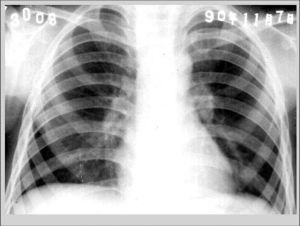

肺門淋巴結核當機體尚未產生變態反應時,肺內初感染原發灶中結核菌借淋巴流侵入所屬淋巴結。從肺門到縱隔有許多淋巴結。病勢進展時,縱隔淋巴結也相繼發病,形成各種不同程度的乾酪化,從肺淋巴結流借肺門縱隔淋巴結,最後多從右靜脈角淋巴流入肺靜脈內,故結核菌隨其易於流入血流。因此,肺門淋巴結核是處於容易發生潛在性菌血症的狀態。

1.胸部X線或CT掃描明確有無肺結構的損害。